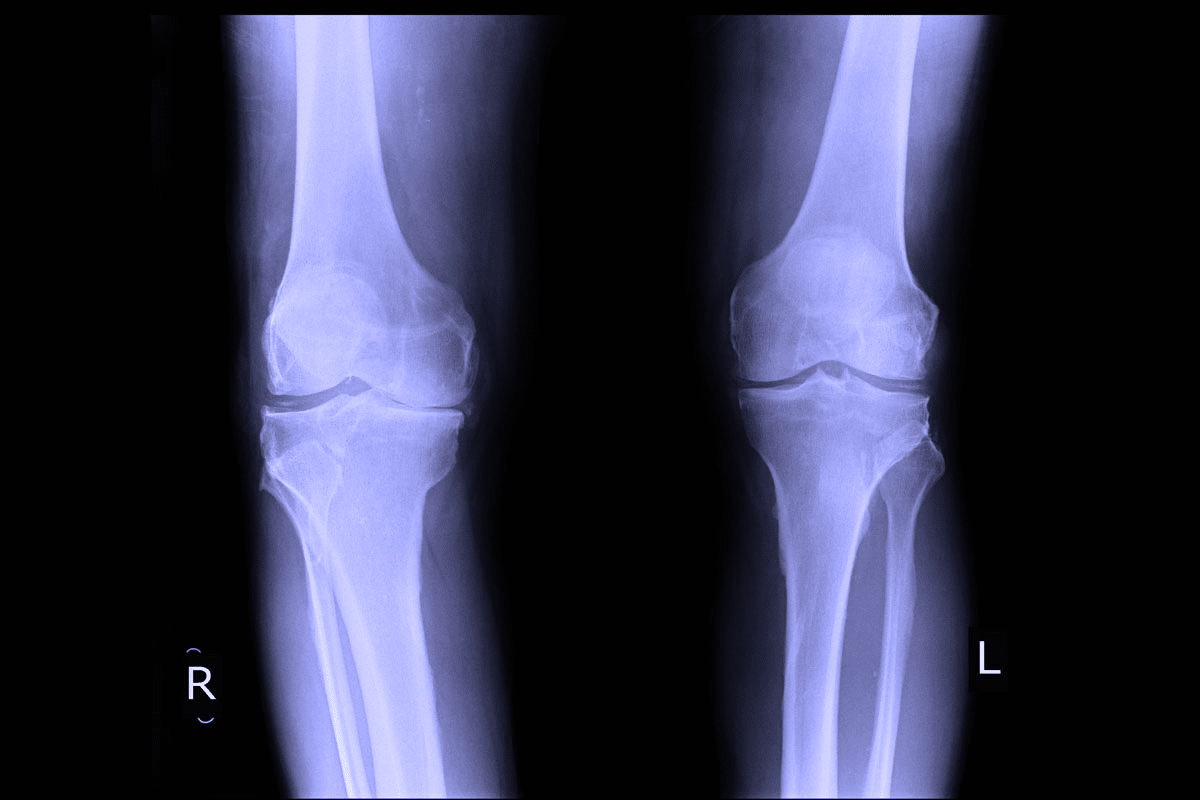

• X-rays: Used to see any existing damage to the bone or cartilage, helping the doctor track how the disease has progressed over time.